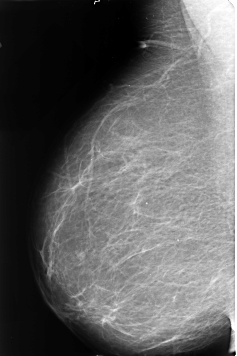

B_3478_1.RIGHT_MLO

LEFT_MLO LINES 4704 PIXELS_PER_LINE 3208 BITS_PER_PIXEL 12 RESOLUTION 50 OVERLAY

FILE: B_3478_1.LEFT_MLO.OVERLAY

TOTAL_ABNORMALITIES 1

ABNORMALITY 1

LESION_TYPE MASS SHAPE IRREGULAR MARGINS ILL_DEFINED-SPICULATED

ASSESSMENT 4

SUBTLETY 5

PATHOLOGY MALIGNANT

TOTAL_OUTLINES 1

BOUNDARY